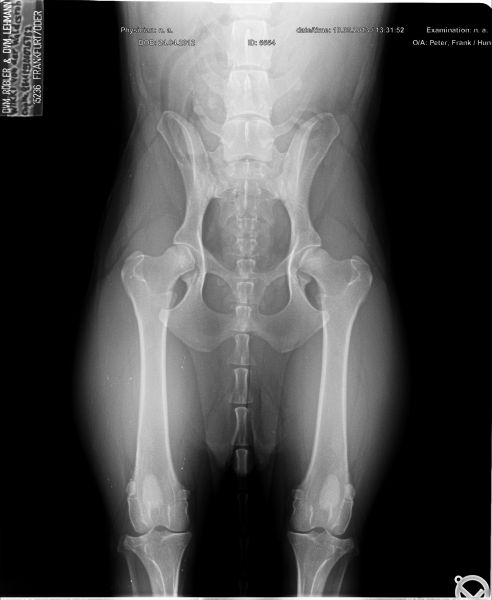

Auswertung der Röntgenbilder von Wikki  aus Augsburg:

HD- fast normal; ED-normal